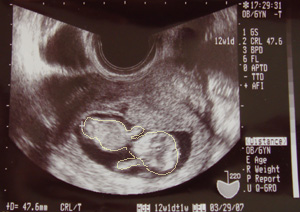

←手ができていた。*画像クリックで大きくなります

右側の円が頭で、左が胴。その下が足になるところかな。

人の形をしてきたことに神秘を感じる。